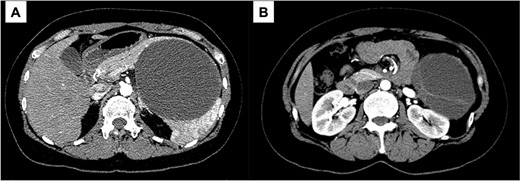

A 43-year-old woman visited our hospital because of abdominal pain. Her medical history was unremarkable and not suggestive of acute pancreatitis or cholelithiasis. Laboratory studies revealed slight anemia and normal levels of amylase and inflammatory markers. Contrast-enhanced computed tomography (CT) showed a multilocular cystic lesion with a septum and a small, hyperdense area suggestive of intratumoral bleeding (Fig. 1). Magnetic resonance imaging (MRI) revealed a multilocular cystic lesion with a thick septum on T2-weighted imaging (Fig. 2). Those findings suggested a pancreatic cystic tumor, including the possibility of MCN, and we decided to perform distal pancreatectomy with splenectomy. A midline incision was made in the upper abdomen. A 15-cm tumor was identified in the tail of the pancreas, displacing the stomach and body of the pancreas. We mobilized the tumor in the tail of the pancreas along with the pancreatic body and spleen en bloc from the retroperitoneum. The tumor was extirpated by dissecting the body of the pancreas (Fig. 3).

Contrast-enhanced CT; (A) the large cystic lesion in the pancreatic tail has displaced the stomach and the body of the pancreas; (B) the wall and septum show enhancement.